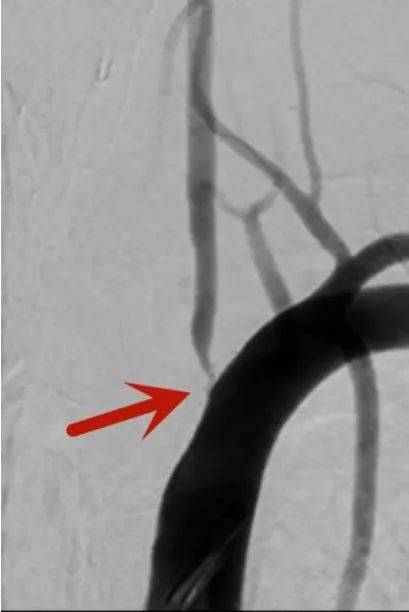

70岁的王先生,因反复头晕半月余,来到北京中医医药大学东方医院秦皇岛医院(秦皇岛市中医医院)就诊,经脑血管造影检查,确诊为“左侧椎动脉重度狭窄”,且狭窄程度大于90%。

术前

术后

北京中医药大学东方医院脑血管病专家刘佳霖带领脑外科团队为王先生成功实施了椎动脉支架植入术,手术顺利,术后椎动脉狭窄解除,头晕症状完全改善。